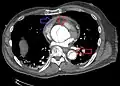

Stanford type B dissection of the descending part of the aorta (3), which starts from the left subclavian artery and extends to the abdominal aorta (4). The ascending aorta (1) and aortic arch (2) shown in the image are not involved in this condition.